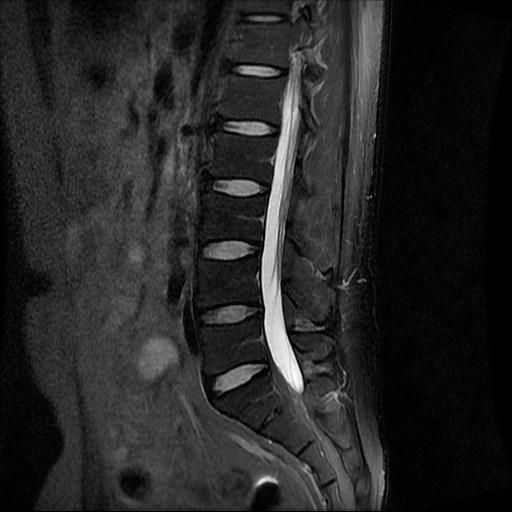

허리 MRI 디스크 상태 분석 부탁드립니다

검진 차 MRI찍었는데 분석 부탁드립니다.

건협에서는 관리해야 된다는데 디스크 협착이나 팽윤 등이 있는 상태인지 궁금합니다.

우선 현재로썬 사진만으론 판단을 하기에 제한이 되지만 사진상 디스크 상태는 심해보이지 않습니다.

요추부위의 하부 에서 약간의 팽윤이나 돌출로 의심해볼수 있는 정도이지만, 정확한 상태는 관련 전문의에게 진료시 문의를 하시는 것을 추천드립니다.